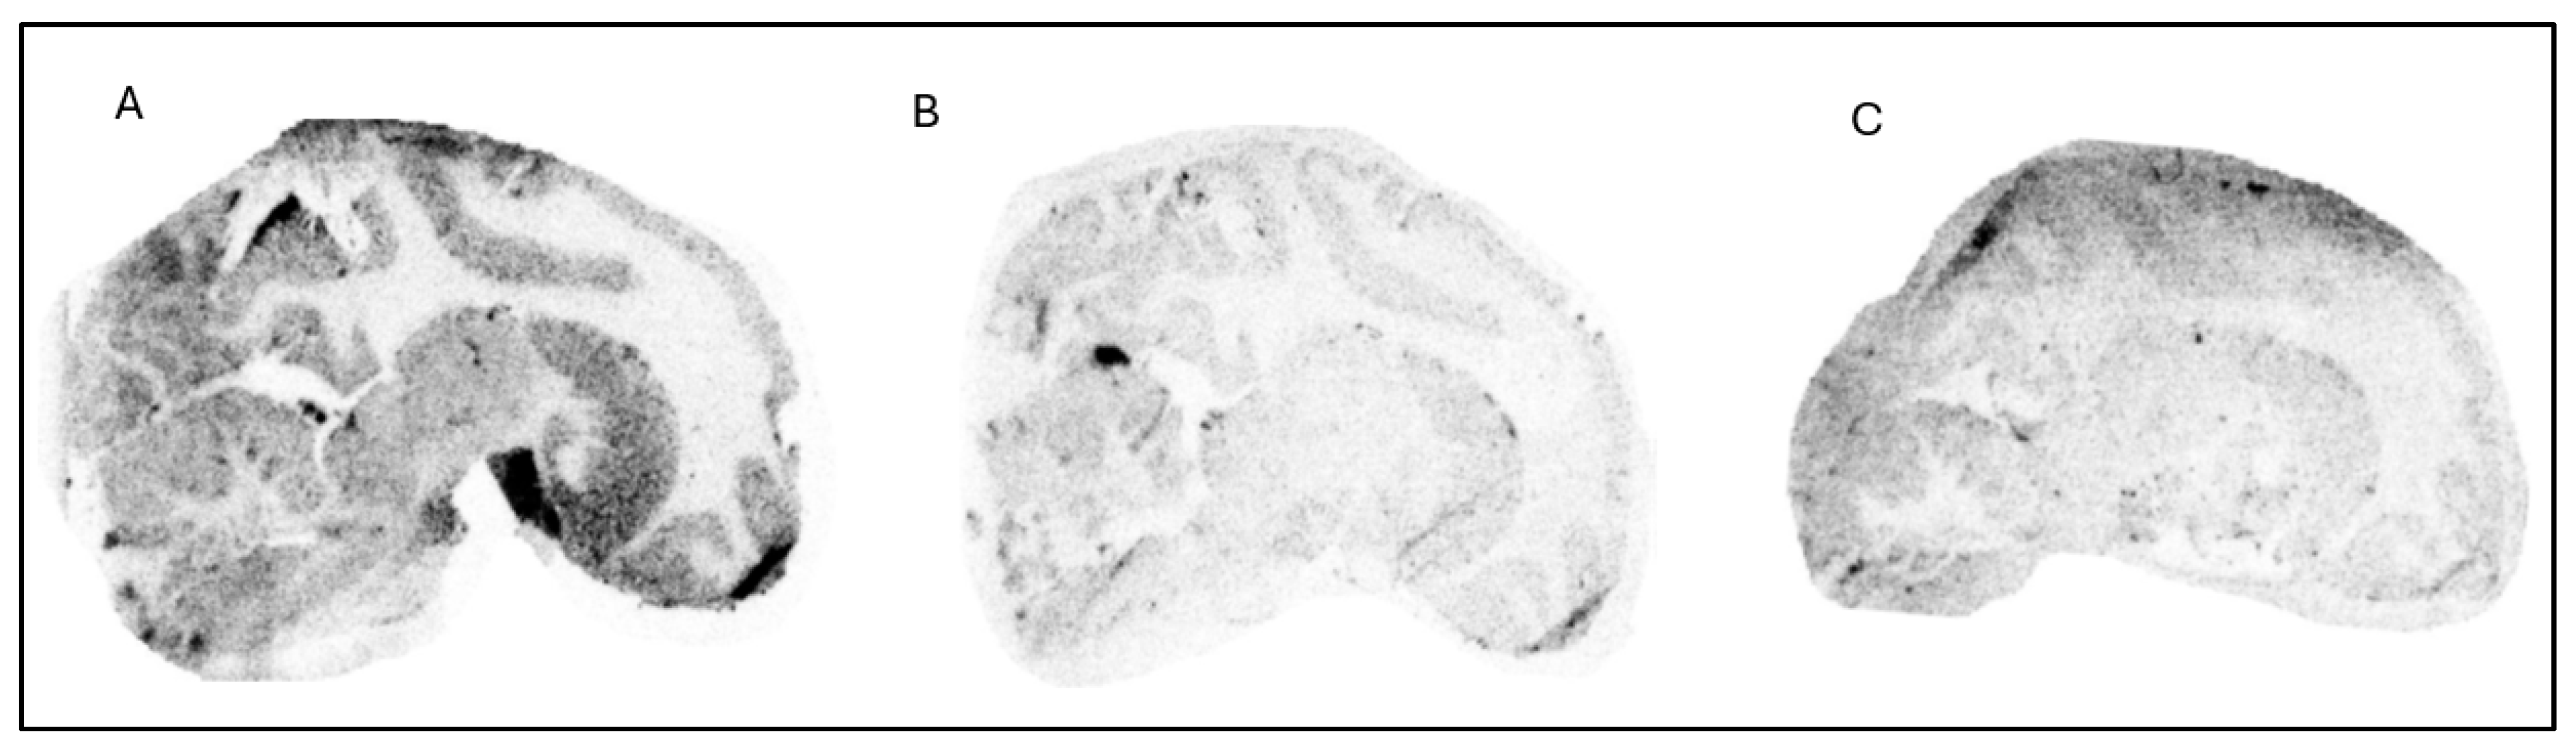

The in vitro ARG studies aimed to assess the binding characteristics of the compounds; [18F]1 displayed clear binding in brain slices from NHP (Figure 2) and human (Figure 3). The binding was effectively blocked by an excess of cold Compound 1 (self-block) as well as Compound 3 (heterologous block), indicating that its interaction with brain tissue is likely specific. However, pre-incubation with 0.1 µM of PFE-360 [20], another structurally different LRRK2 kinase inhibitor, did not significantly reduce the binding of [18F]1 in a human brain slice (Figure 4). This could indicate that [18F]1 exhibited limited specificity but more likely that the concentration of PFE-360 used may have been suboptimal, as Compound 2 demonstrated significant blocking activity at 10 µM.

Figure 2. Autoradiograms of sagittal slices of a NHP brain labeled with [18F]1 at baseline condition (A) and during incubation with cold Compound 1 (10 µM) (B) and Compound 3 (10 µM) (C).